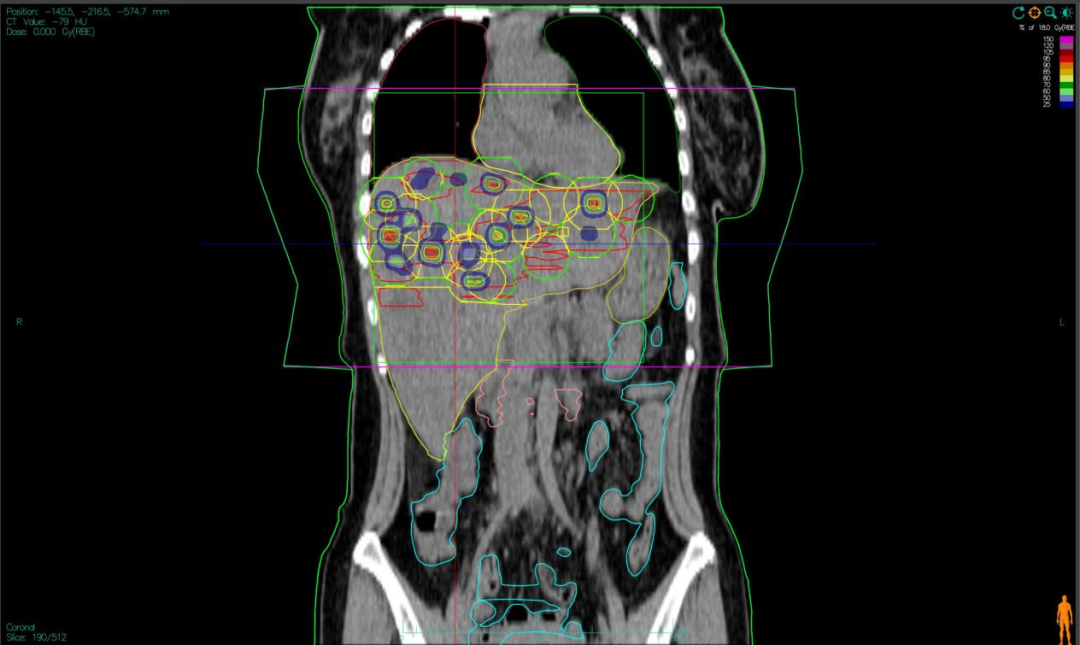

患者:女,四十三岁,晚期胰腺神经内分泌癌伴肝巨大转移,病情已至危重阶段。胰腺原发病灶伴随肝脏内弥漫性、部分融合成团的巨大转移灶,几乎取代正常肝组织。受巨大肿瘤负荷与受损肝功能影响,她彻底失去手术与常规化疗的机会。面对这一绝境,我院团队将其视为践行前沿整合治疗理念的契机,为她量身打造以“双‘布拉格’晶格放疗”为核心的个体化治疗方案。

二,采用“晶格放疗”先进布野技术,在巨大肝肿瘤内部精准布设能量“棋盘格”,在高效杀伤肿瘤细胞的同时,为残存正常肝组织与关键脉管留存生存空间;

三,将此次精准物理打击,完美嵌入“布拉格治疗”免疫协同策略,以此作为激活全身免疫反应的“点火器”,联合PD-1抑制剂与GM-CSF,力求激发远隔效应,对未被照射的病灶形成攻击;